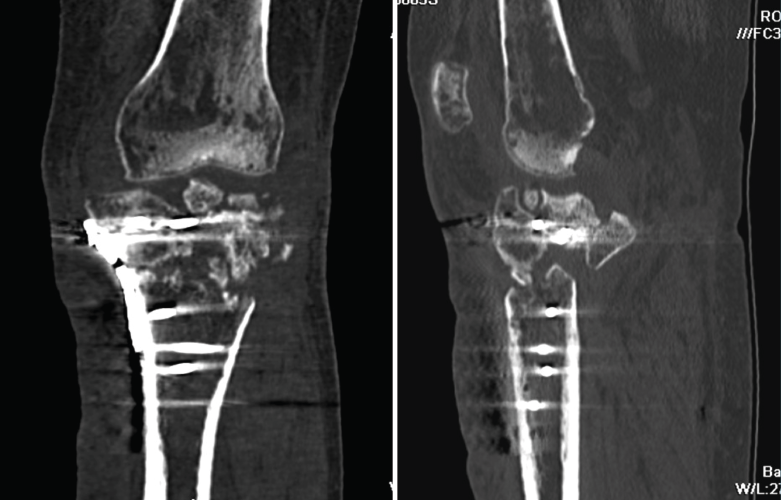

2. Complicaciones de las fracturas

2.1. Injertos

En las fracturas que requieren un aporte de injerto, la TAC es útil para valorar el porcentaje de su asimilación al hueso (Figura 21).

Figura 21. Corte de reconstrucción sagital y coronal de tomografía axial computarizada de rodilla: fragmentos cálcicos incorporados a la medular tibial diafisaria.

2.2. Pseudoartrosis

La pseudoartrosis se define cuando, transcurridos al menos 6 meses desde la fractura, no se produce su consolidación y se evidencian muy pocos o ninguno de los signos de evolución radiográfica (Figura 22).

Figura 22. Corte de reconstrucción coronal y sagital de tomografía axial computarizada de rodilla: fractura metafisoepifisaria tibial sin consolidación después de 6 meses.

2.3. Retardo de la consolidación

El retardo de la consolidación es un enlentecimiento de la velocidad esperada (de 3 a 6 meses) del proceso de consolidación de una fractura, pero esta llegará a producirse de forma normal y definitiva (Figura 23).

Figura 23. Corte de reconstrucción coronal y sagital de tomografía axial computarizada de rodilla: fractura de epífisis proximal tibial con puente óseo insuficiente por retraso de la consolidación.

2.4. Consolidación viciosa

Se produce cuando los fragmentos consolidan en mala posición, con deformidades que alteran el eje del miembro inferior (Figura 24).

Figura 24. Corte de reconstrucción sagital y coronal de tomografía axial computarizada de rodilla: consolidación viciosa de la epífisis tibial proximal.